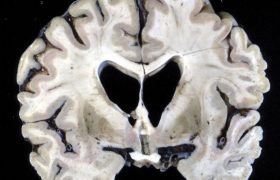

Фокальная корковая атрофия, редкое нейродегенеративное заболевание. Данный вид деменций ассоциирован с накоплением тау-протеина в нейронах теменно-затылочной и височной областей. Причины избирательных атрофий отдельных участков головного мозга на данный момент неясны. Ряд исследователей относит их к атипичным формам болезни Альцгеймера или кортикобазальной дегенерации.

Первоначальными проявлениями являются зрительная агнозия и апраксия.